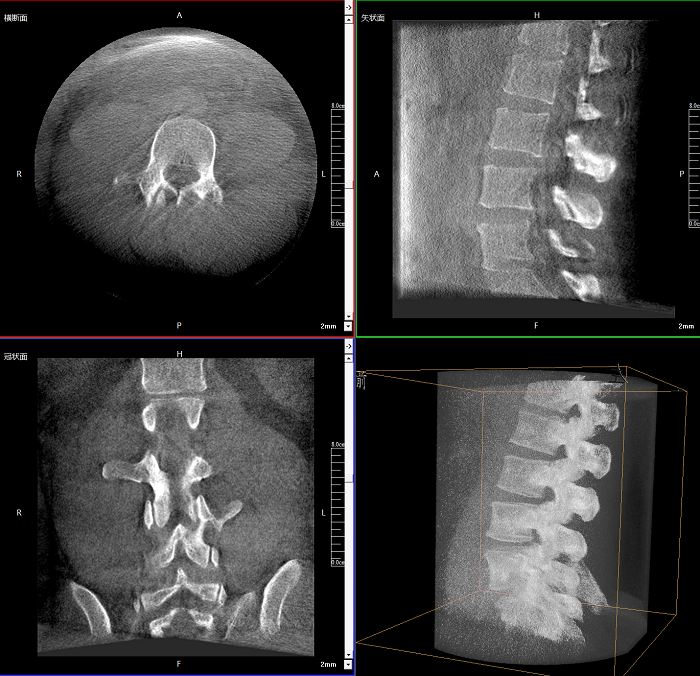

三維成像 全面觀察

任意視角、任意切面觀察

術(shù)中實(shí)時(shí)生成橫斷面、矢狀面、冠狀面及三維影像,可在任意切面、任意角度評(píng)估植入物和解剖結(jié)構(gòu)的相對(duì)位置。

Clinical picture

臨床圖片